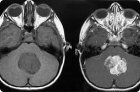

Американские научные работники пришли к выводу о том, что люди, часто делающие у стоматолога обыкновенные рентгеновские снимки собственных челюстей, в большей степени рискуют обрести менингиому - доброкачественная опухоль, растущая из паутинной мозговой оболочки.

Менингиома считается доброкачественной опухолью. Она увеличивается довольно медленно и вовсе не считается столь уж опасной угрозой для организма человека. Хотя в отдельных случаях она приводит к инвалидности и практически стопроцентной утрате трудоспособности